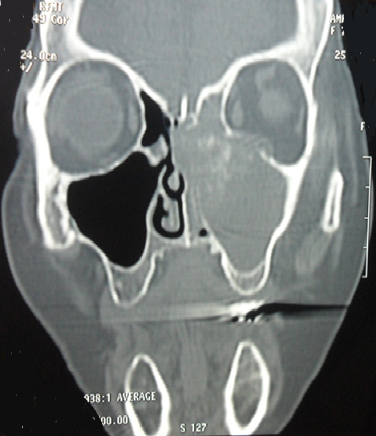

Les sinusites aspergillaires invasives sont des infections fongiques opportunistes rares, rapidement extensives de pronostic redoutable. Elles surviennent préférentiellement sur un terrain d'immunodépression. Leur présentation clinique et radiologique est peu spécifique. Le diagnostic positif est orienté par l'imagerie mais sa confirmation est anatomopathologique et/ou mycologique. Seule une prise en charge médico-chirurgicale rapide et adéquate permettra un meilleur pronostic chez les patients atteints de cette infection. Patient âgé de 60 ans, suivi pour un diabète de type 2, a consulté pour des douleurs rétro-orbitaires gauches avec œdème palpébral homolatéral et fièvre évoluant depuis 7 jours. L'examen physique a trouvé un œdème palpébral, un ptosis et une rougeur oculaire. L'endoscopie nasale a objectivé une muqueuse congestive et nécrosée. L'examen biologique a montré des valeurs glycémiques très élevée. La TDM du massif facial a révélé une sinusite ethmoïdo-maxillaire gauche avec épaississement des tissus mous palpébraux gauches et une infiltration de la graisse extra-conique. Plusieurs diagnostics ont été évoqués notamment un lymphome, une tuberculose ou une néoplasie solide. L'examen mycologique a confirmé la présence de filaments mycéliens d'Aspergillus fumigatus. Il a eu une ethmoïdectomie gauche avec excision des lésions nécrotiques par voie endonasale. Le traitement médical s'est basé sur l'amphotéricine B et l'insulinothérapie pour équilibrer son diabète. L'examen anatomopathologique a conclut à une nécrose de la muqueuse nasale avec présence de nombreux filaments mycéliens. L'évolution était favorable avec un recul de 2 ans.